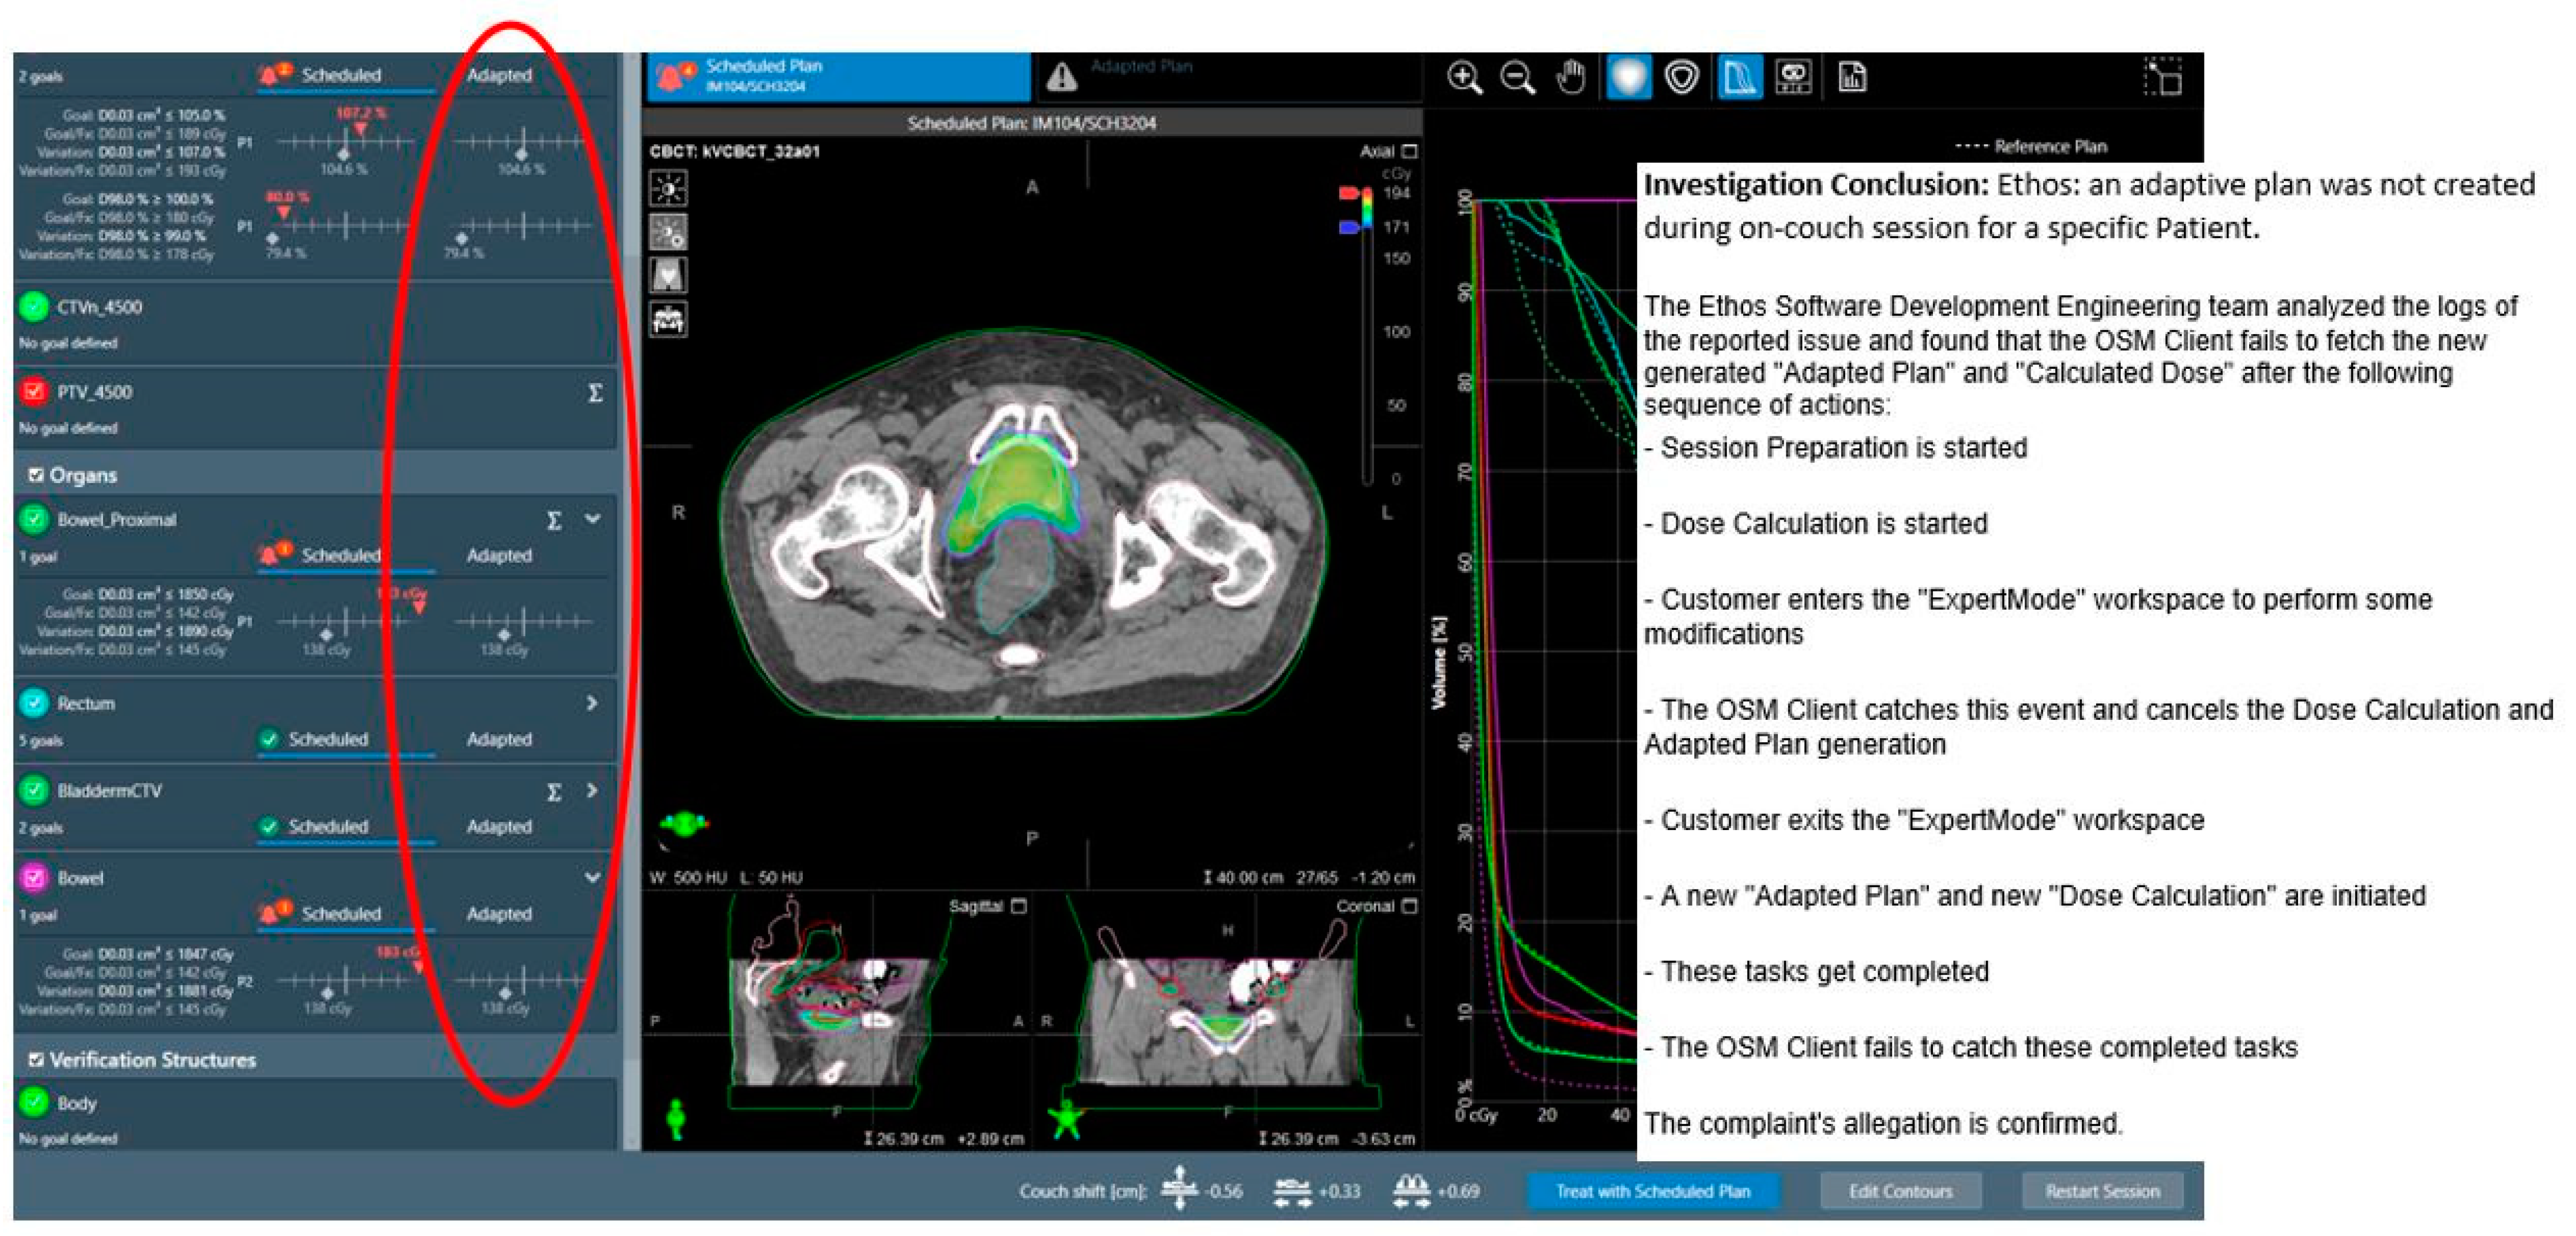

3.2.1. System-Driven Issues

| Adaptive plan unavailability due to internal software communication issues | 0.1% (1 instance) | N/A |